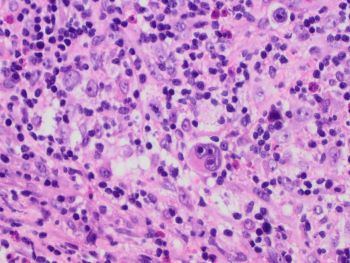

Images 1 and 2 show an enlarged lymph node with mostly intact architecture and marked paracortical expansion with pale staining areas. The expansion is mostly nodular. Although, areas of diffuse paracortical expansion are seen, such as on the left side of image 2. Images 3 and 4 show pale staining areas at high power magnification from different parts of the lymph node. Image 3 shows Langerhans and interdigitating dendritic cells with mostly small lymphocytes in the background. Image 4 shows Reed Sternberg cells with a mixed background of histiocytes, small lymphocytes, eosinophils, and plasma cells.

CD30 is positive in the Reed Sternberg cells of CHL and negative in Langerhans/dendritic cells. CD15 is not as helpful since it is negative in about 1/4 of CHL. CD20 is usually negative in CHL and would not help distinguish. CD3 would be negative in both, and both would show a similar background rich in T-cells.

CHL is part of the differential diagnosis for dermatopathic lymphadenopathy (DL). The pale areas can resemble the Reed Sternberg cells and histiocytes of CHL and vice versa. An added challenge is when CHL shows an interfollicular growth pattern (seen in this case) without marked distortion of the lymph node architecture. provides an extra challenge in showing relatively preserved nodal architecture. High power examination of the pale areas for Reed Sternberg cells will distinguish the two with immunohistochemical studies performed if needed (CD15, CD30, PAX5, CD45, etc.).

This case presents a situation where DL is not just a mimic of CHL, and the lymphoma be overlooked without thorough examination of the entire lymph node.